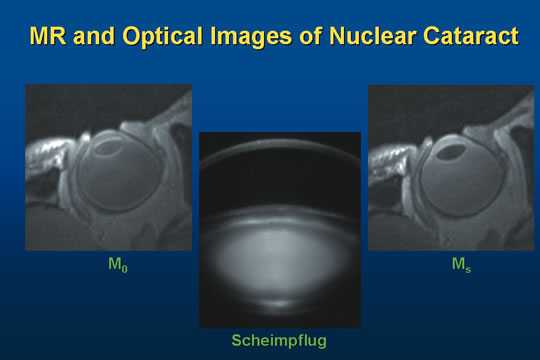

in the lens.70  Fig. 12. Sagittal section images of a nuclear cataract. M0: Magnetic resonance image (MRI) of a patient's eye with

a nuclear cataract, taken in vivo and noninvasively. Scheimpflug: Image of the same nuclear cataract (LOCS II nuclear opalescence

grade 2) taken using a Zeiss Scheimpflug slit lamp camera (optical/digital). Ms: MRI image of the same eye with magnetic transfer contrast (MTC) enhancement (see

text). Fig. 12. Sagittal section images of a nuclear cataract. M0: Magnetic resonance image (MRI) of a patient's eye with

a nuclear cataract, taken in vivo and noninvasively. Scheimpflug: Image of the same nuclear cataract (LOCS II nuclear opalescence

grade 2) taken using a Zeiss Scheimpflug slit lamp camera (optical/digital). Ms: MRI image of the same eye with magnetic transfer contrast (MTC) enhancement (see

text).

|